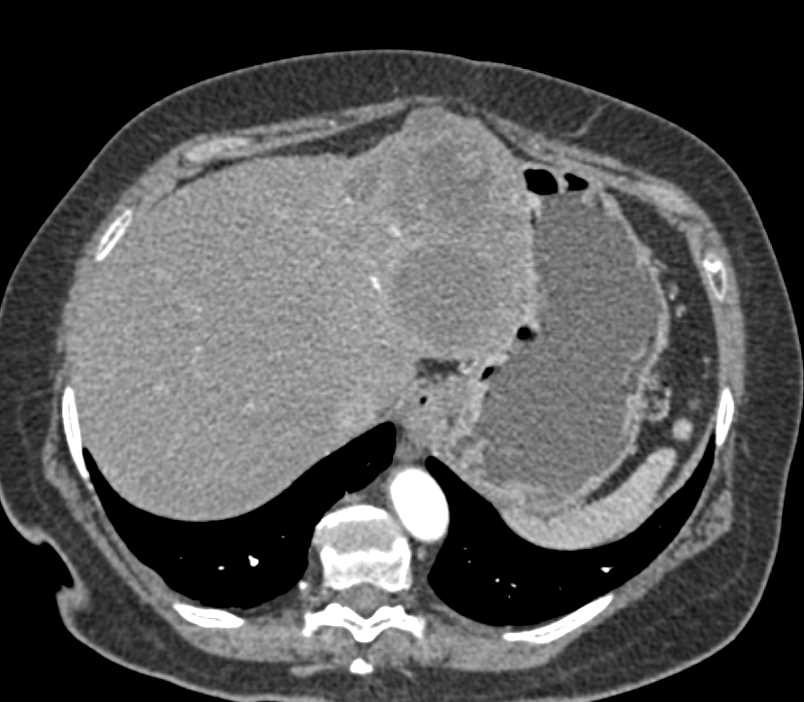

Hemangioma Left Lobe of Liver